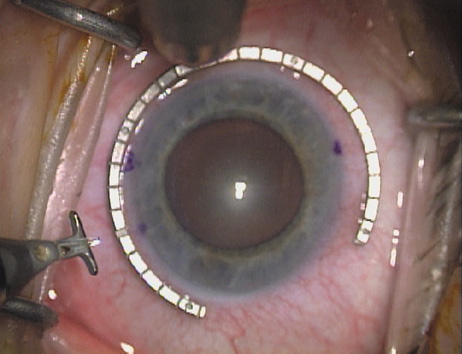

Case 2 is a 79-year-old woman who presented with a very dense left cataract. Her refraction was recorded at −2.25 +2.75 × 125 with a difficult end point. Her manual keratometry and topography measurements were consistent and revealed slightly less than 1.75 D at 120 degrees. Because of the questionable refraction, greater value was placed on the corneal measurements. Based upon the cataract nomogram, the plan was for paired LRIs of 40 degrees to be placed over the steep 120-degree axis (Figs. 1219).

Fig. 12. In this left eye, the steep meridian is at the 120-degree axis and has been delineated by opposing limbal marks. The upper left hand ink mark represents the 6:00 position for orientation. (Reprinted from Hardten DR, Lindstrom RL, Davis EA. Phakic Intraocular Lenses: Principles and Practice. Thorofare, NJ: SLACK Incorporated, 2004, with permission.)

Fig. 13. The incision is begun 20-degrees to one side of the centering mark. (Reprinted from Hardten DR, Lindstrom RL, Davis EA. Phakic Intraocular Lenses: Principles and Practice. Thorofare, NJ: SLACK Incorporated, 2004, with permission.)